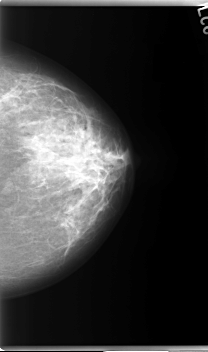

C_0032_1.LEFT_MLO

LEFT_MLO LINES 5896 PIXELS_PER_LINE 3344 BITS_PER_PIXEL 12 RESOLUTION 50 NON_OVERLAY